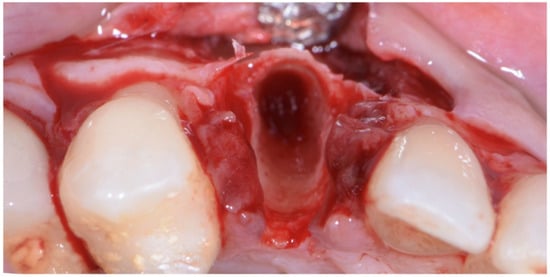

The surgical technique consisted in the execution of a lateral-approach coronally advanced envelope flap, which requires oblique submarginal interproximal incisions directed towards the flap’s center of rotation (in this case, the tooth to be extracted) (Figure 4a,b); the latter start from the gingival margin of the adjacent tooth and end at a distance from the vertex of the papilla that should equal the desired amount of coronal advancement of the marginal tissues. The flap was elevated in a split–full–split manner; a split-thickness incision was performed at the level of the surgical papillae by keeping the blade parallel to the bone; then, the central portion of the buccal flap was elevated in full thickness with a periosteal elevator until 2–3 mm of buccal bone was exposed. Apically, flap elevation continued, first with a “deep” split-thickness incision, keeping the blade parallel to the osseous plane and detaching the muscle insertions from the periosteum, and afterwards with a “superficial” one, placing the blade parallel to the external mucosal surface and controlling its movement using transparency while detaching the superficial muscle insertions from the inner aspect of the flap. This last incision is the one responsible for flap mobility [17]. Once the buccal flap was elevated, the atraumatic extraction of the canine was performed (Figure 5). Full visibility and access help to avoid both trauma to the anatomical papillae and damage to the buccal bone plate; special attention should be placed towards preserving the integrity of the anatomical papillae mesial and distal with respect to the canine, since they are essential for the surgery’s successful outcome.

Figure 5. Atraumatic extraction of canine after buccal-flap elevation.